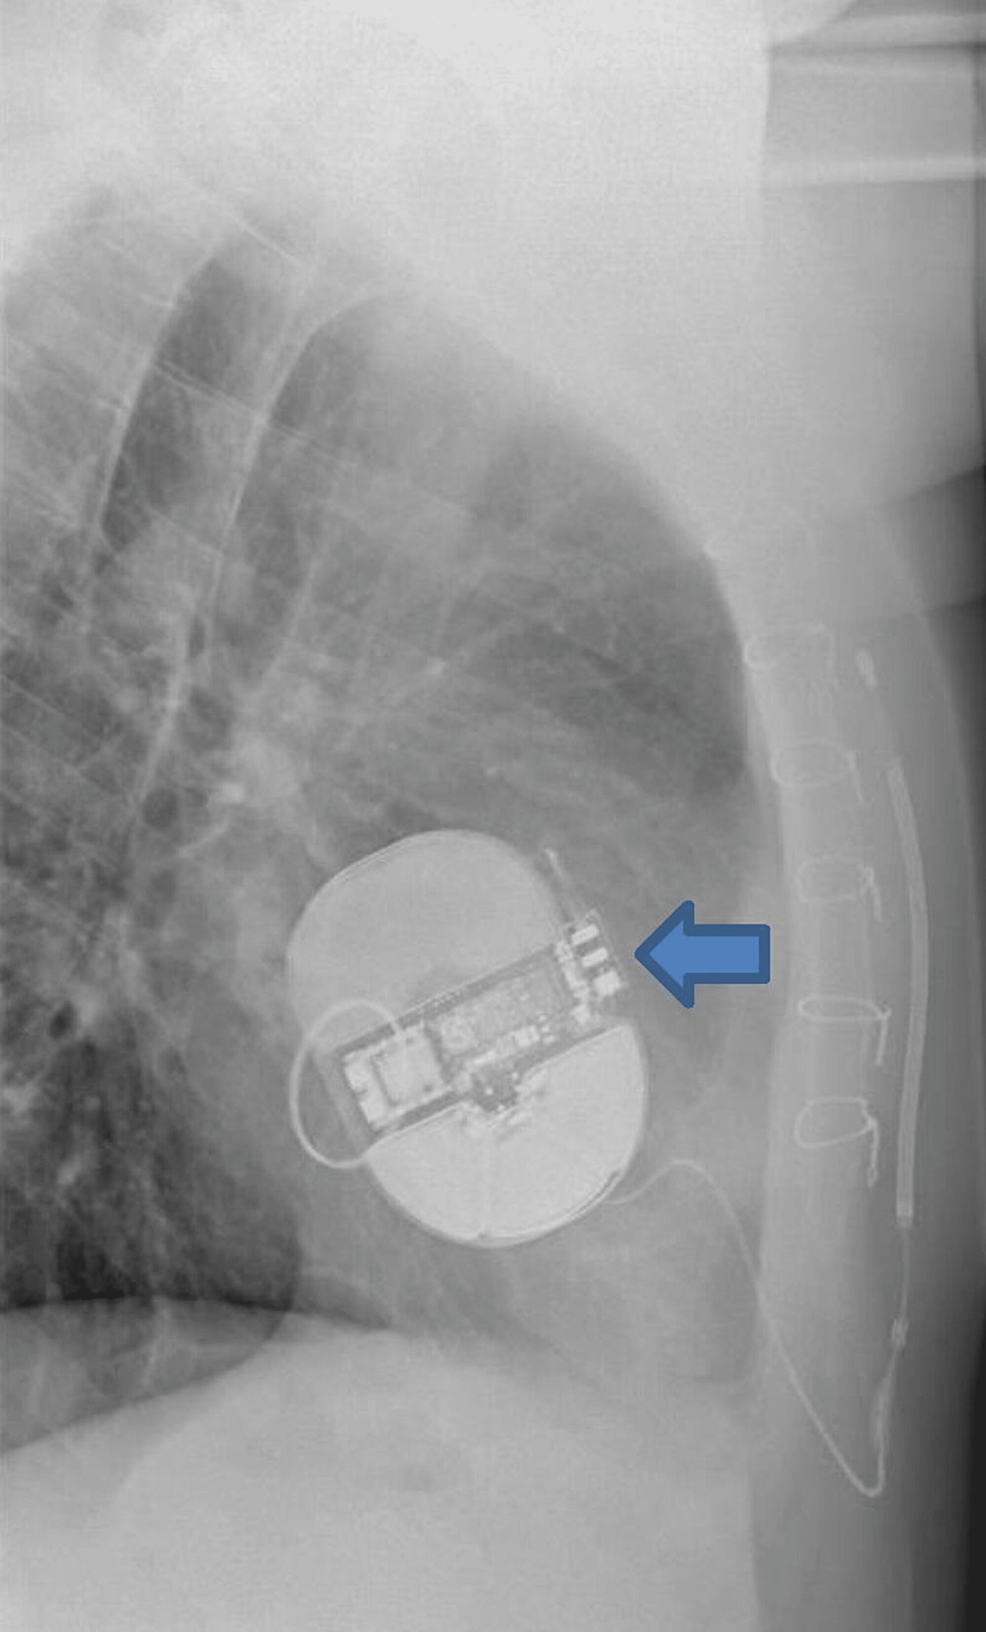

From www.researchgate.net

Preoperative chest Xray showing the automatic implantable cardioverter Defibrillator Implant Shock Learn about the indications, types, and complications of icd shock, and how to monitor and manage patients with icds. The leads are wires with electrodes. Icd shock is an electric therapy delivered by an implantable cardioverter defibrillator (icd) to restore a regular heart rhythm. Learn how an implantable cardioverter defibrillator (icd) monitors and corrects abnormal heart rhythms, and what to. Defibrillator Implant Shock.